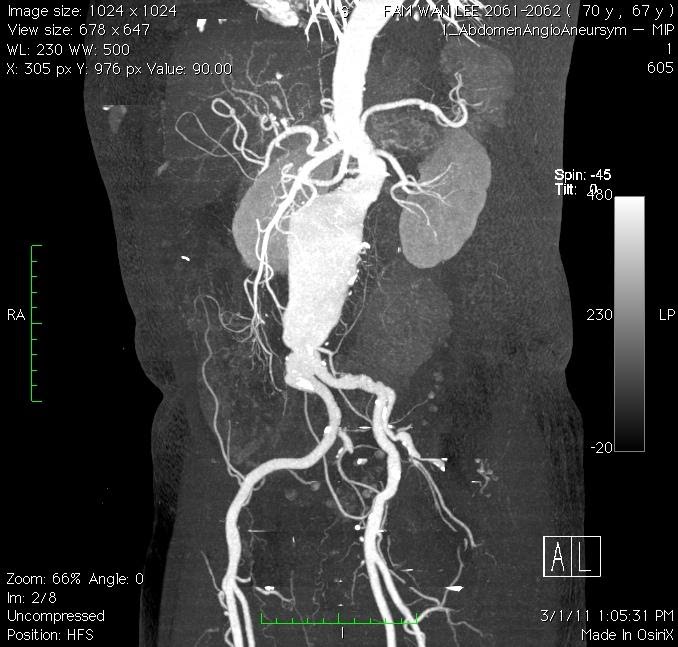

Modern diagnostic tools like ultrasonography (Figure 1) and computed tomography (CT) scan (Figure 2) makes the diagnosis much easier. The reported prevalence is around 4-8% in male and 1-2% in female after 70 year old. With ages beyond 80, the male to female ratio almost became 1:1.

Figure 2. CT scan delineates the anatomy of AAA

Abnormal dilatation of a vessel wall, more than 50% of its normal diameter is considered as aneurysm. Abdominal Aortic Aneurysm (AAA) is abnormal dilatation of abdominal aorta, more than 3cm in diameter. Commonest area involved is infra-renal aorta. (Figure 3)

In order to prepare for EVAR, patient diagnosed with AAA needed a Computed tomography angiogram (CTA) with EVAR protocol. This enables the operative surgeon to calculate accurately on the size and type of stent graft needed, expecting possible difficulty and complication and hence improving the outcome of intervention.

The morphology of AAA is an important factor to decide on EVAR treatment. Infra-renal normal aortic segment of 20mm length, aneurysm-neck angle of less than 60 degrees, peri-aortic neck thrombus, tortousity of Iliac access artery and diameter of iliac artery used to be very strict criteria to decide on suitability of candidate for EVAR treatment.